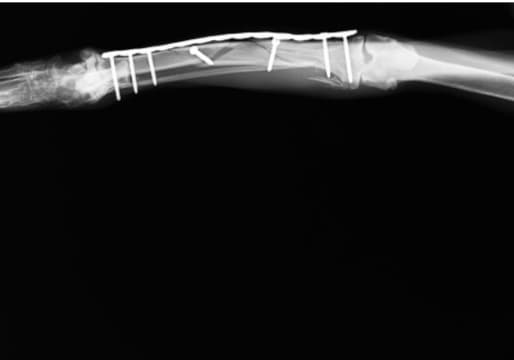

脛骨高平部水平化骨切り術(TPLO)は、脛骨を切ってプレートで固定することにより、脛骨の頭側への移動を防ぎ、膝を安定化させる手術です。

8kgを超えるワンちゃんには、この術式で行うことが多いです。